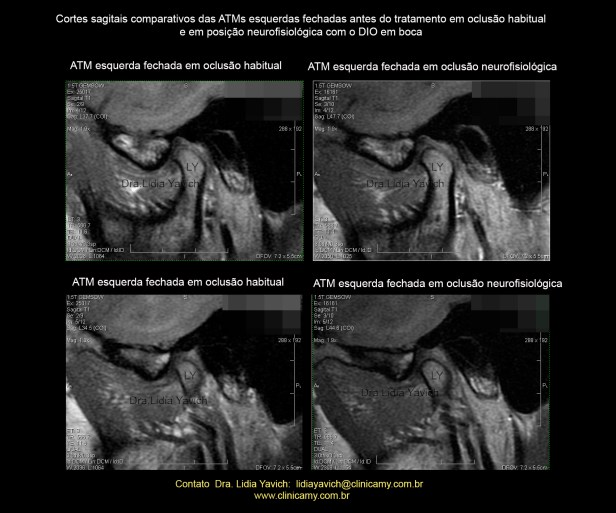

RNM da ATM esquerda:

Corte sagital em boca fechada: existe uma ante-versão do côndilo mandibular, discreta retificação da sua porção ântero-superior.

Cortes sagitais comparativas das ATMs esquerdas em boca fechada antes do tratamento em oclusão habitual e em posição neurofisiológica com o DIO em boca.